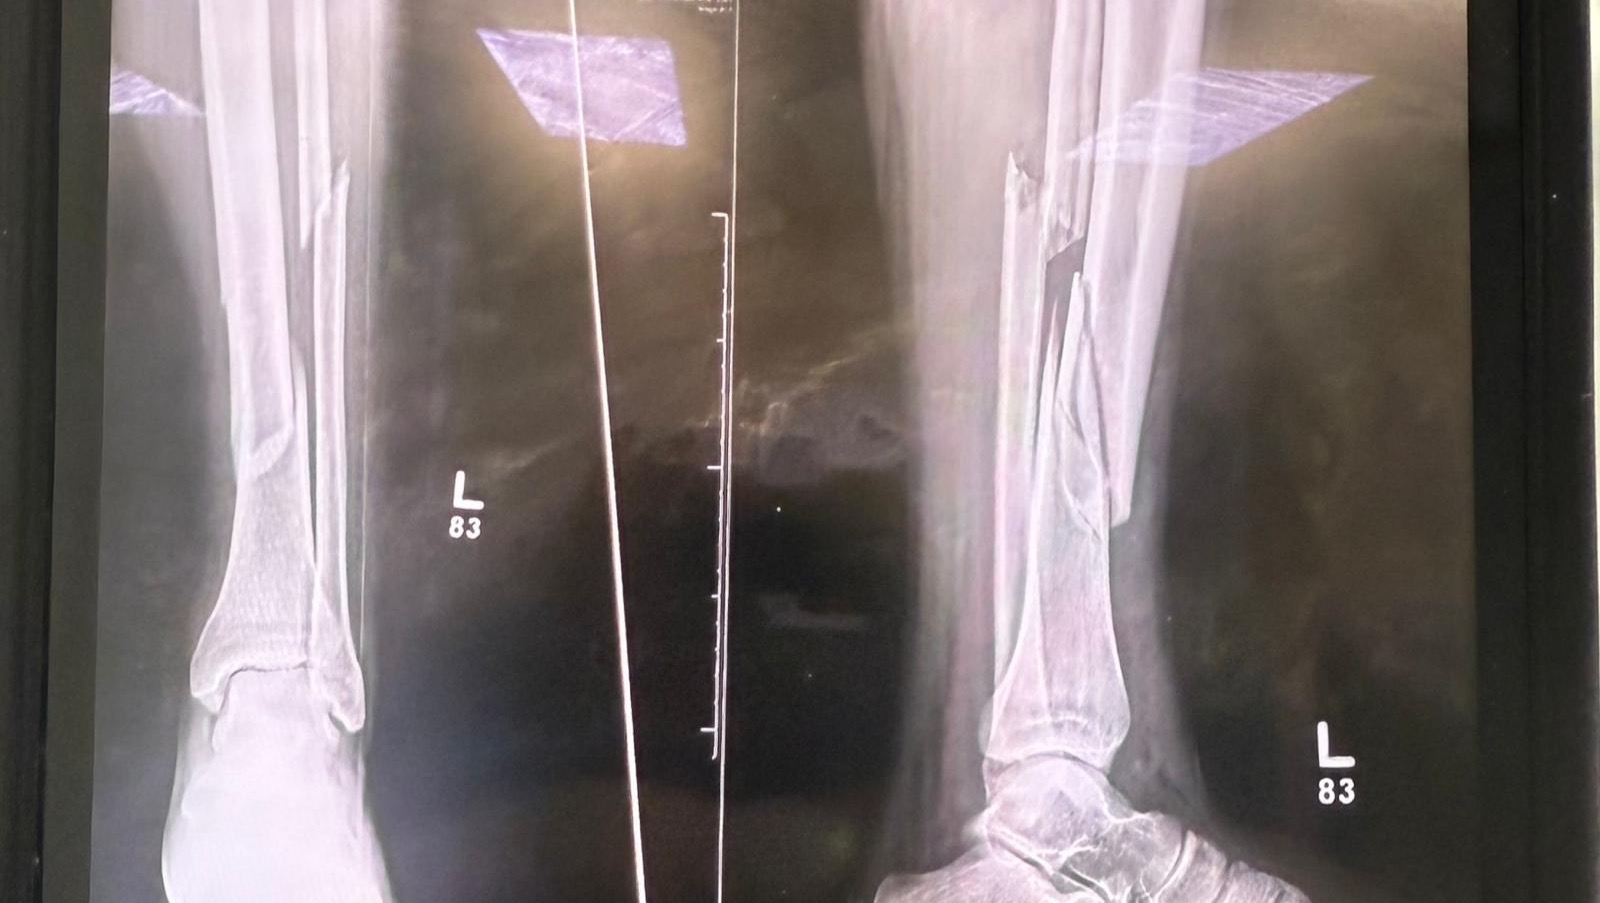

Hi, my name is Gley, and I’m asking for your support after a recent accident that has left my husband severely injured. Yesterday, he fell during a boating trip and broke his leg. He will need surgery, including screws to rehabilitate his walking. Because of this he will be unable to work for a long time and may lose his job.

Hola, mi nombre es Gley y estoy pidiendo su apoyo después de un accidente reciente que dejó a mi esposo gravemente herido. Ayer, él se cayó durante un paseo en bote y se rompió la pierna. Necesitará cirugía, incluyendo tornillos para rehabilitar su capacidad de caminar. Debido a esto, no podrá trabajar por un largo tiempo y puede perder su empleo.